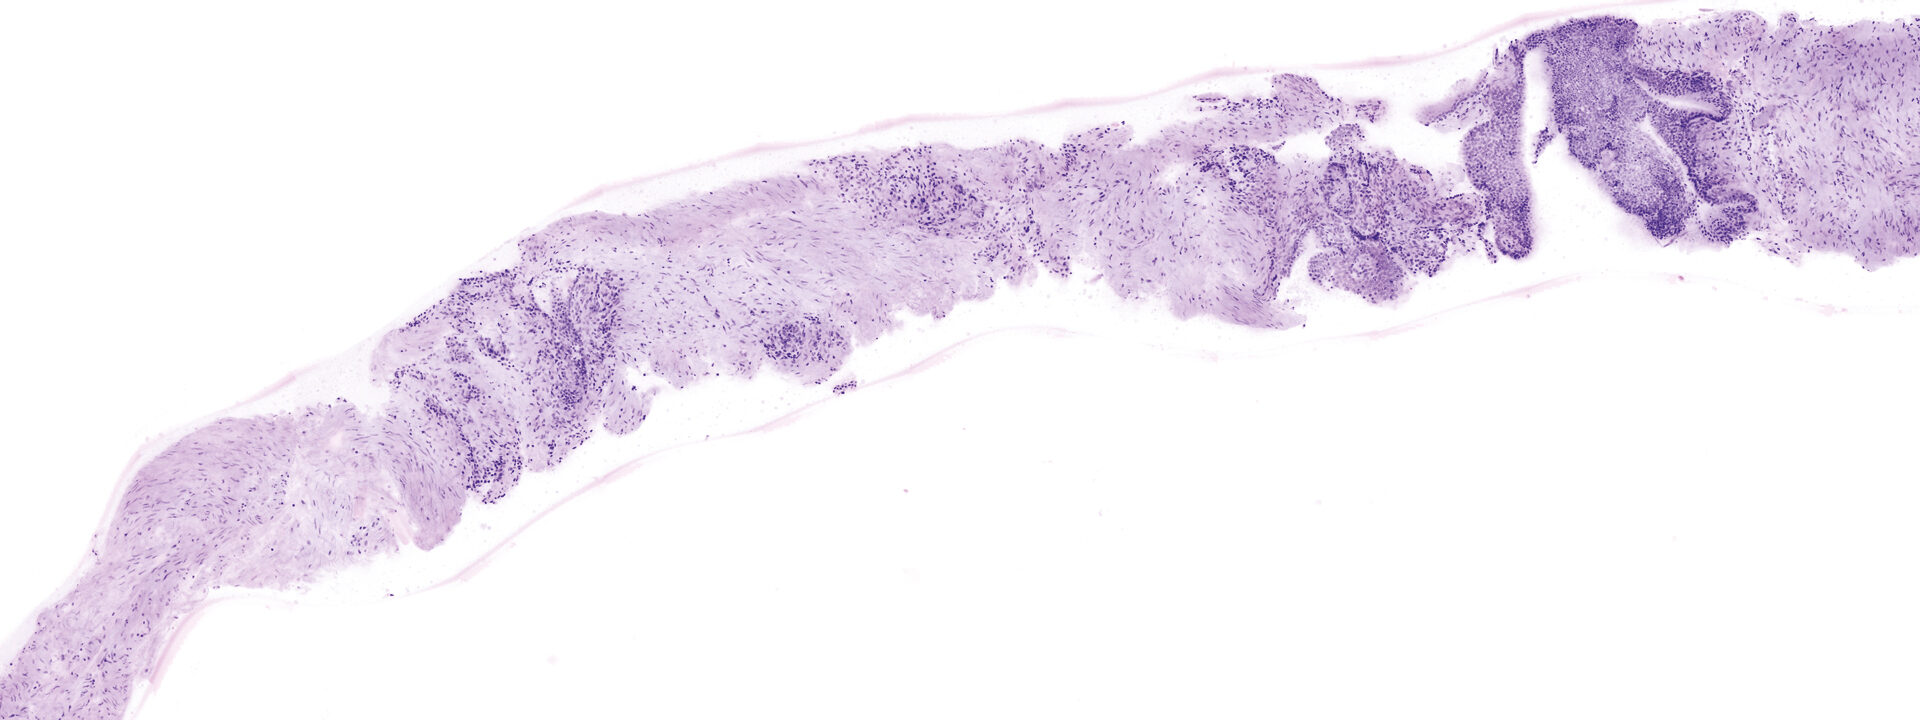

See every detail. Seamless zoom up to 550x. With a great sample size.

The VivaScope technology is based on confocal microscopy (CLSM) and acquires images of superb optical resolution and contrast. The VivaScope 2500 images allow seamless zoom with up to 500x magnification and a great sample size.

Image courtesy of Dr Javiera Pérez-Anker, Hospital Clinic of Barcelona.